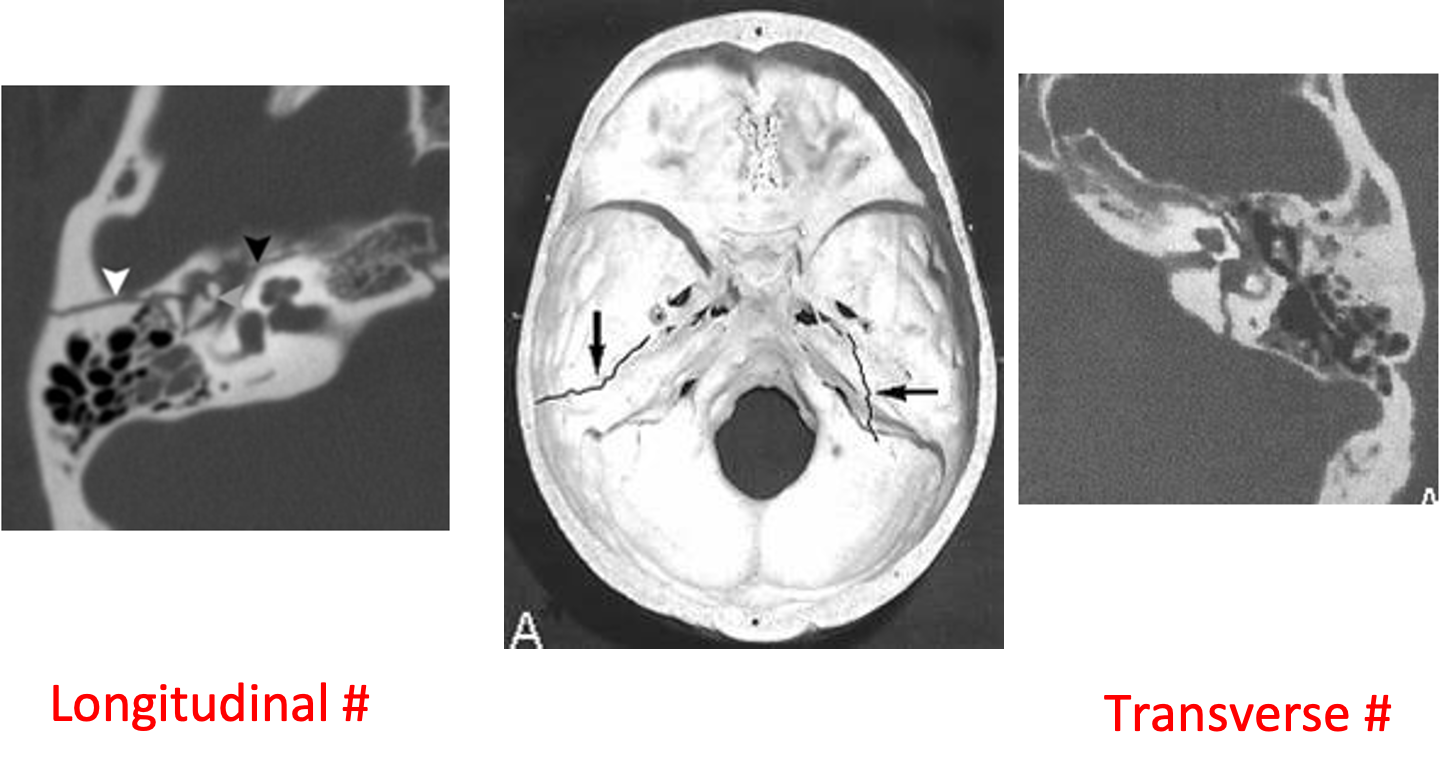

Types of Fractures

Longitudinal fracture - 70%: Conductive hearing loss (rupture drum, hemotympanum or ossicular disruption) - Facial nerve paresis is not common

Transverse fracture - 20%: SNHL & vertigo (Labyrinthine injury) - Facial nerve paralysis is common